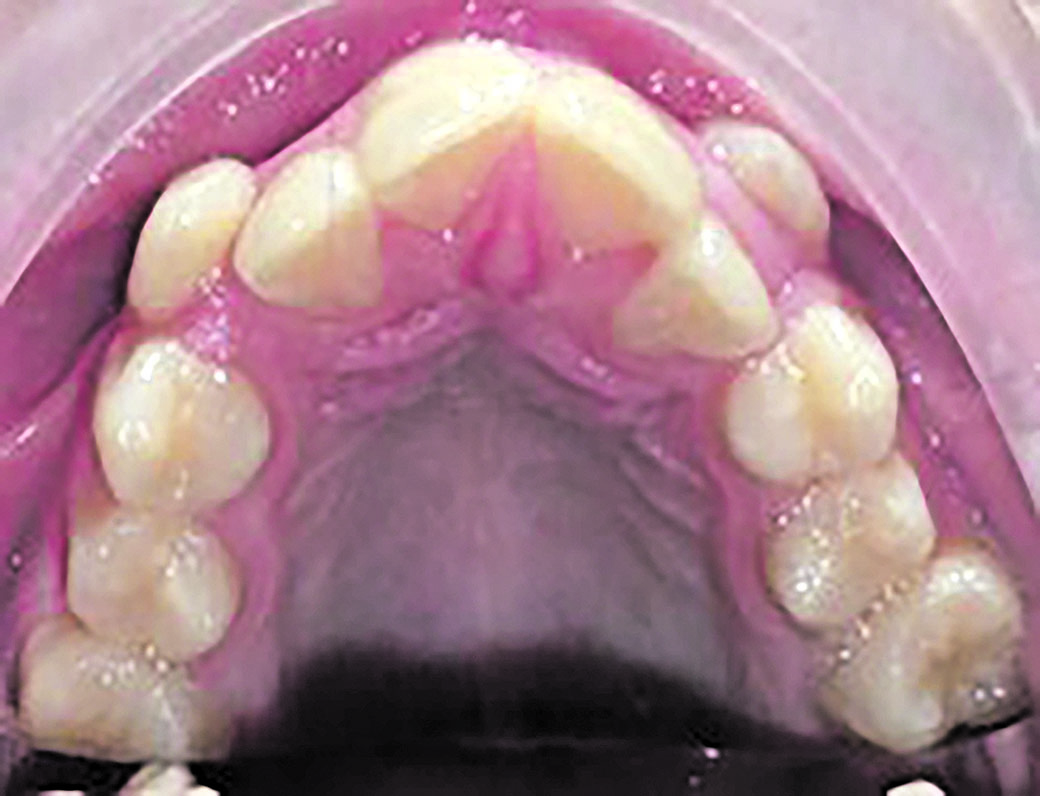

En adults de vegades ens trobem amb maloclusions importants on hi ha alteracions en la posició de les dents, en l’estructura dental, en la geniva, en els maxil·lars, en l’articulació temporomandibular, en la funció masticatòria, en la respiració... Casos molt complexos.

Hi ha estudis on s’evidencia com amb una dieta primitiva hi ha un bon desenvolupament cranial, de les arcades dentals, bona condició física i immunitat als processos degeneratius moderns com l’artritis, malalties cardíaques i afeccions internes. En aquest mateix estudi es veu com els fills d’aquestes poblacions que canvien d’hàbits dietètics i d’estil de vida perden aquesta immunitat, així com els empitjora el desenvolupament facial i la forma dels arcs dentals i augmenten les càries.